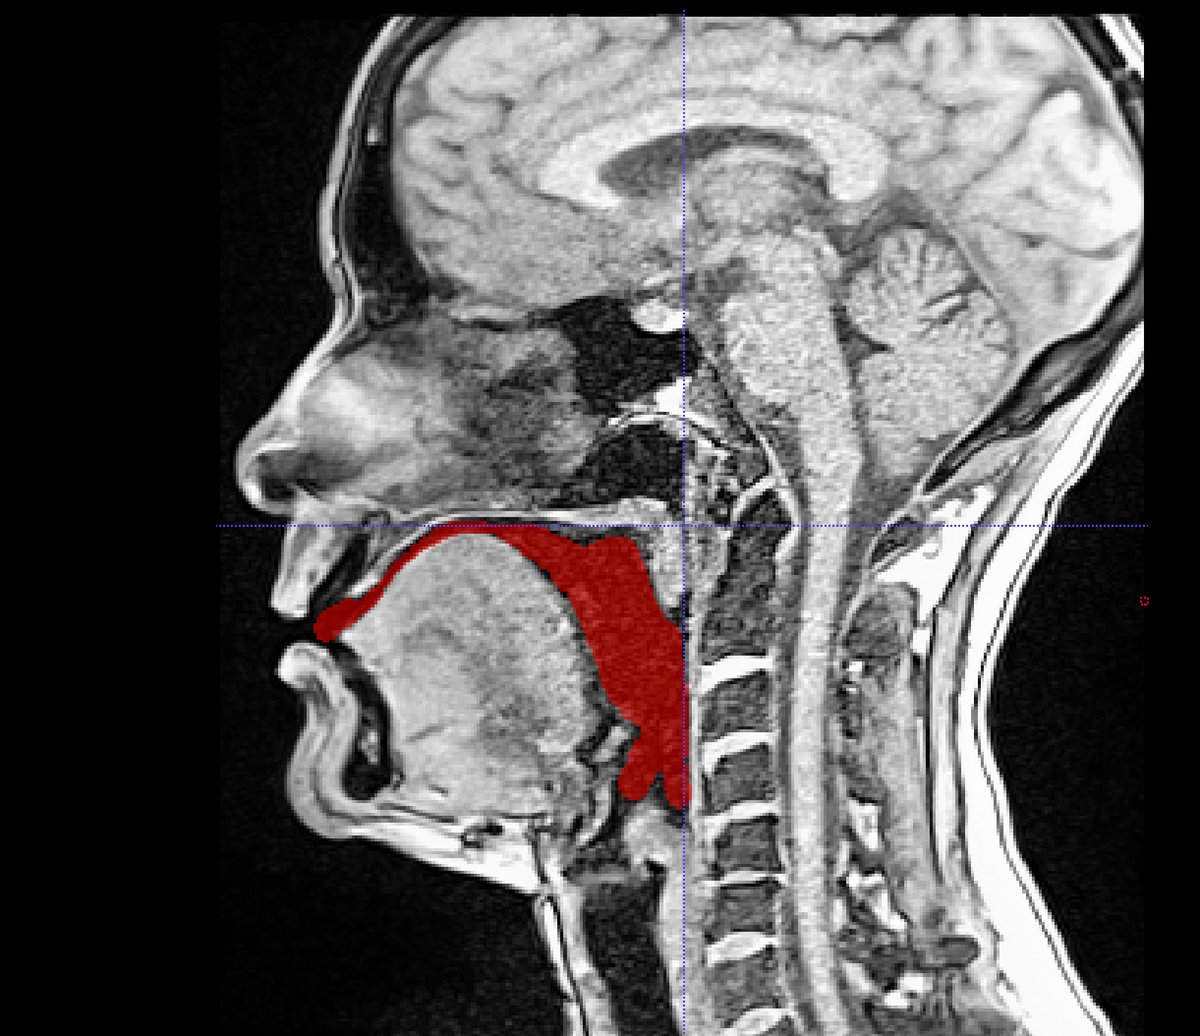

Ce projet vise à expliquer la production des sons au grand public. Les données IRM nous permettent d'observer la forme du conduit vocal (espace en rouge sur l'image) lors de la production de sons. Cette forme est façonnée par la position des articulateurs qui n'est pas la même en fonction des sons. Vous pouvez voir que l'espace en rouge est différent sur l'image de gauche (correspondant au son [a]) et de droite (correspondant au son [i]).

Une fois cet espace détouré sur les IRM, nous imprimons le conduit.